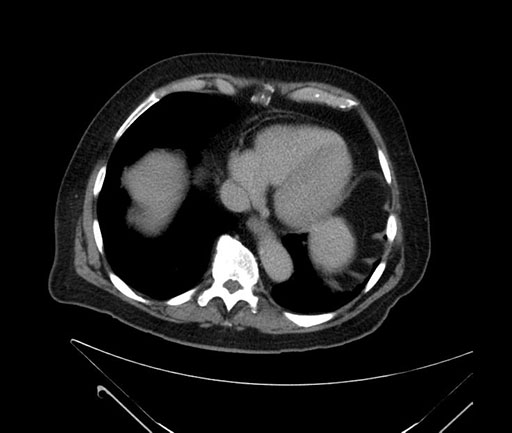

Imaging Analysis

Look through the patient's CT scan to identify any areas of concern for the necessary procedure.

Based on your CT findings, which issue(s) would give reason for "planned slowing down moment(s)" in this case?

Considering a standard Whipple procedure, what step(s) of the operation would you do differently in this case?